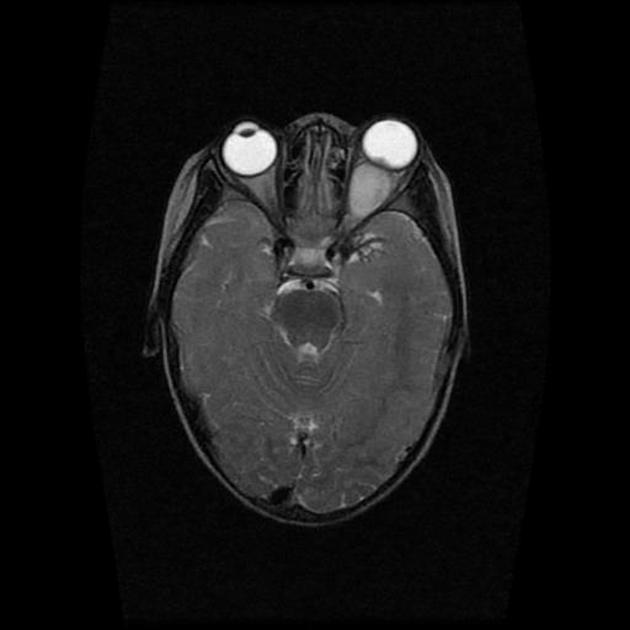

案例七

基本病史:2 岁女孩,摇头,双侧眼球震颤一年余。

图 7 MRI 检查轴位 T2WI 及 T1WI 强化序列显示双侧视神经肿胀呈长 T2 信号,强化呈明显强化,累及视交叉及颅内脑组织